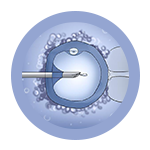

The full form of IVF is In Vitro Fertilization which means the fertilization is carried outside the body. Insemination which means meeting of sperm and the egg is done in a petri dish of a laboratory. For this procedure, eggs from the female are retrieved and at the same time sperms from the male partner are collected. After fertilization of the egg and sperm, the embryo is formed which is transferred in the womb of the female.